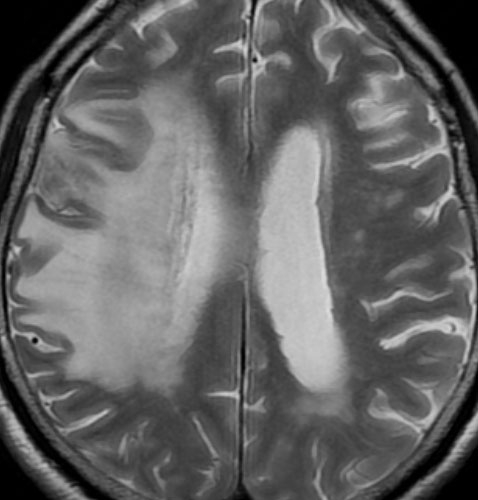

2年後 放射線壊死の進行

定位放射線治療後約2年,前の画像からはわずか3ヶ月後のMRIです。また右前頭葉の転移病巣が再発したかのように見えます。周囲の浮腫も広がって,左の片麻痺が悪化しました。しかし,ガドリニウム増強されて白くリング状に写る部分が不整形でまわりがギザギザしています。ステロイドを投与しましたが改善せずに悪化傾向を示しました。

手術後の脳浮腫の改善

手術で放射線壊死巣を摘出してから1月半後のMRIです。放射線壊死が摘出されて,脳浮腫もかなり改善しました。同時に右麻痺もよくなってきました。